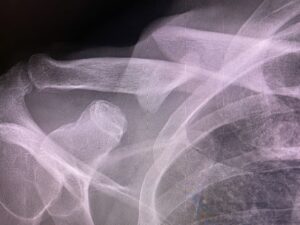

- Imaging findings (X-rays, MRIs, CT scans)

In both workers’ comp and personal injury lawsuits, the burden of proof falls on the injured party. The stronger the documentation of your injury, the stronger your claim. Objective signs help to provide credible and persuasive proof of injury. Using medical illustrations, enlargements of x-rays, MRIs, CT scans and other films can “educate” a judge and jury as to the severity of the injuries sustained. Doug Landau has invested thousands of dollars in medical illustrations, videos and anatomical models that are so realistic and illustrative, that the treating doctors and surgeons have used to teach other physicians after the case is over! Lawyer Landau advances these necessary costs so that his clients will be able to “show and tell: the judge and jury WHY they are in pain, immobilized and unable to go back to their pre-injury jobs and activities, We get 80% of our information through our eyes, so Landau makes sure that jurors and judges hear AND SEE the injuries that the defendant’s unsafe conduct caused.